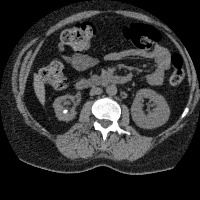

Regiao Renal

RegiaoRenal

regiao_renal